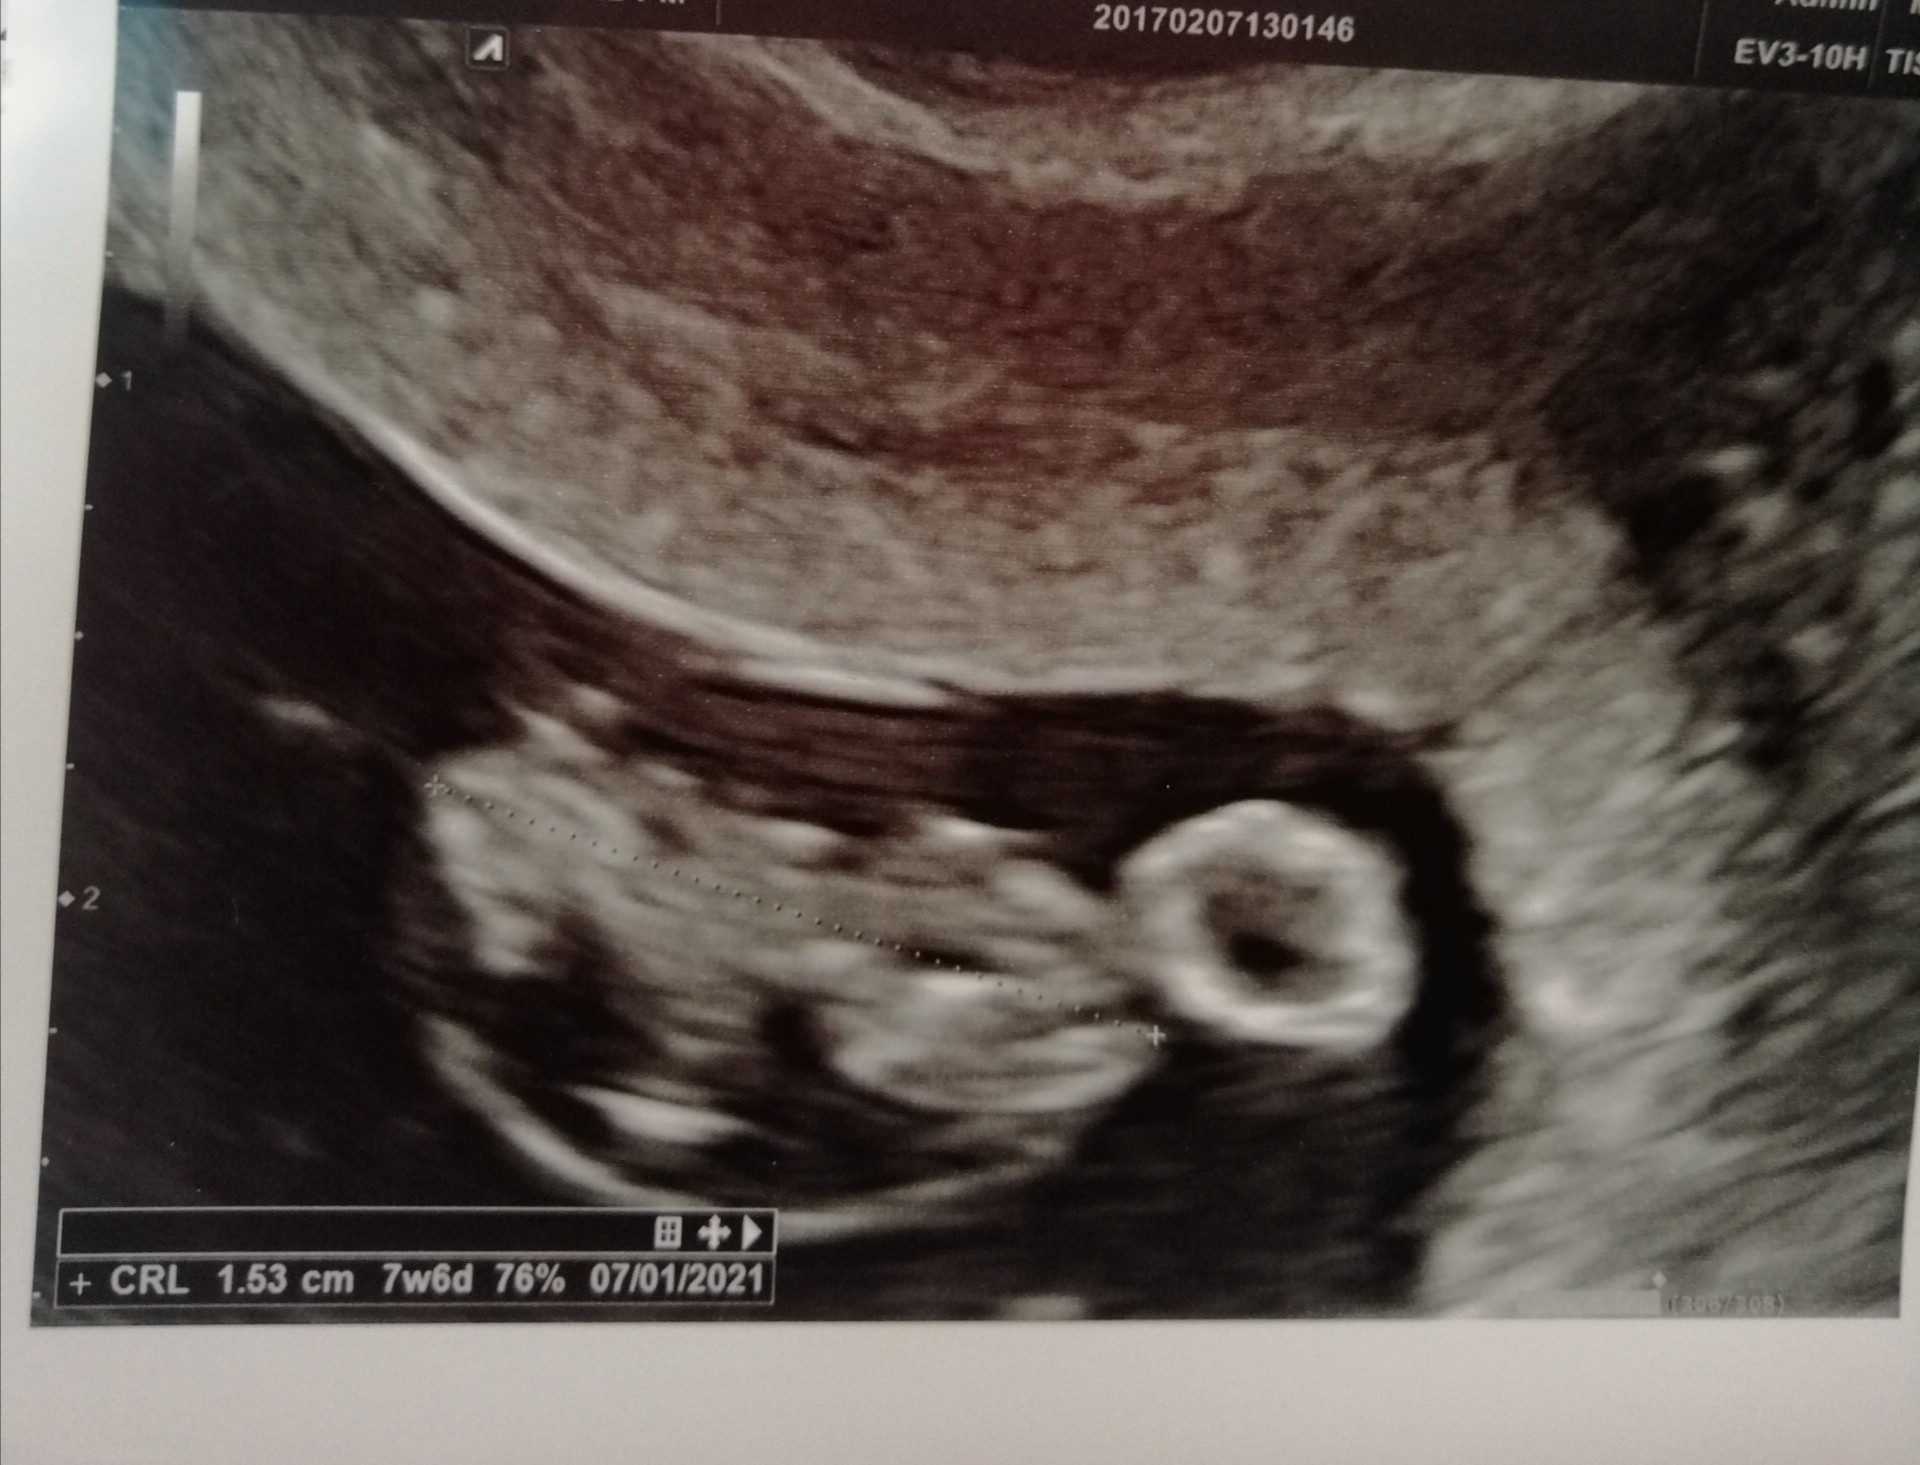

Witam wszystkie mamusie, ja też już po wizycie ☺ u mnie wszystko w najlepszym porządku jak na razie, serduszko bije, chwilkę dał mi doktor posłuchać, uspokoiłam się na najbliższe kilka dni 😀😀